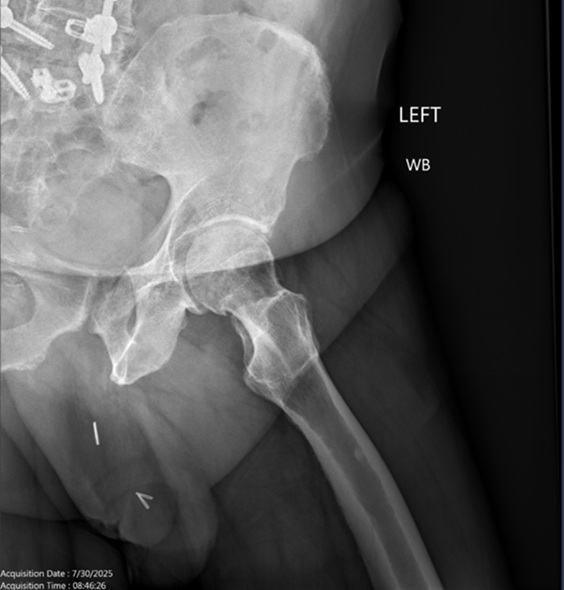

His radiographs in the clinic revealed left hip degenerative joint disease. Additionally, his pre-operative hip MRI revealed significant narrowing of the joint space and femoral head edema securing the diagnosis of degenerative joint disease. His exam was significant for limited internal rotation to no more than 5 degrees, a positive stinchfield test and an antalgic gait.

Radiographs are noted below. Pre-op, Post-op and intra-op radiographs are found below as well as the pre-op MRI.

Figures 1, 2 and 3. AP of the Pelvis, AP of the Left Hip, and a Frog Leg Lateral of the Left Hip demonstrating left hip osteoarthritis.

Figure 3.